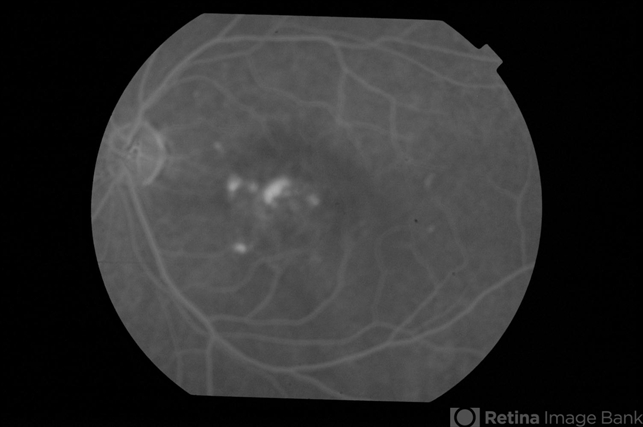

- CSCR subfoveal leak

- 52-year-old male with left eye CSCR of 6 months duration. Late phase fluorescein angiogram shows multiple leaks including a sub-foveal one. He was treated with PDT with complete resolution of fluid.